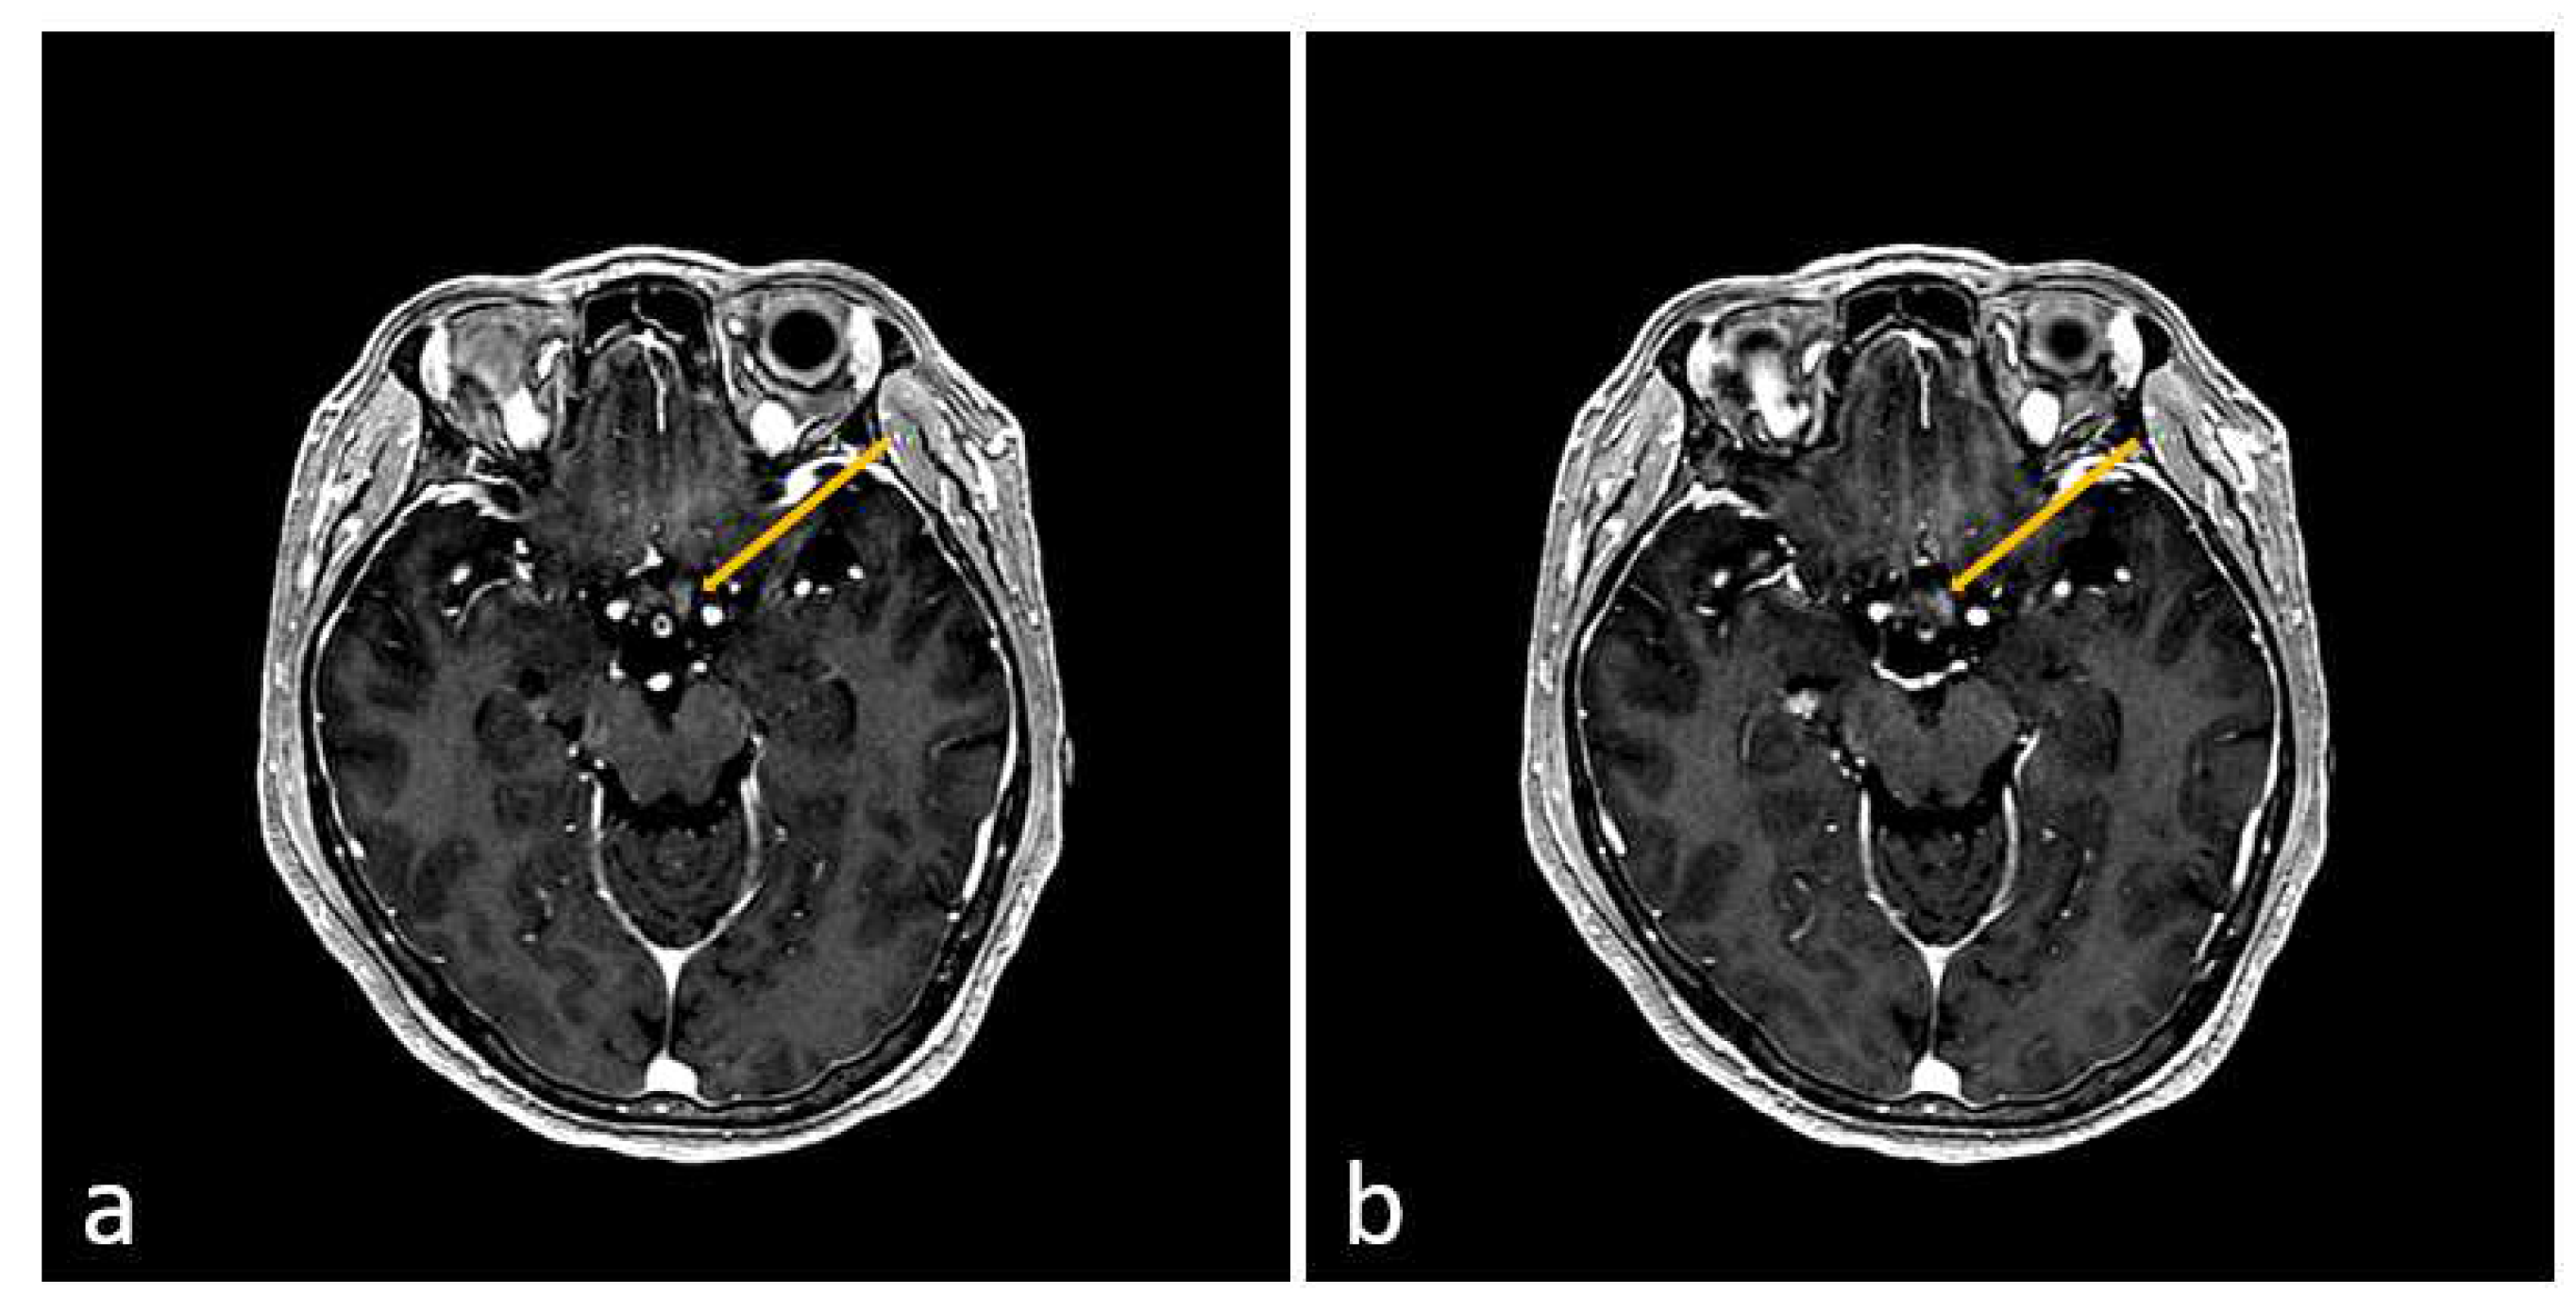

2. Case Presentation